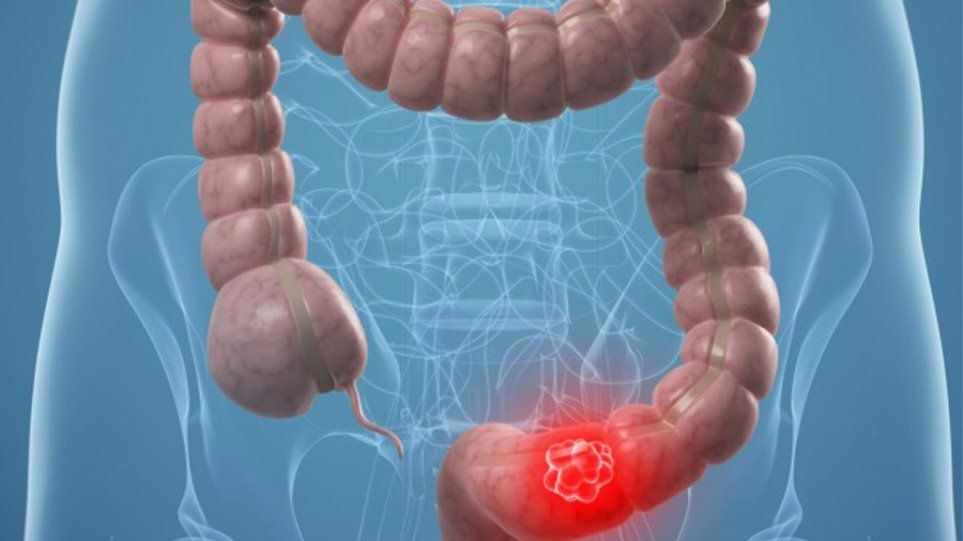

Ο καρκίνος των ωοθηκών, του παχέος εντέρου και του μαστού είναι οι πιο συχνοί κληρονομούμενοι καρκίνοι. Συγκεκριμένα μεταξύ των κληρονομούμενων καρκίνων το ποσοστό του καρκίνου των ωοθηκών κυμαίνεται μεταξύ 15 έως 25% ενώ ακολουθεί ο καρκίνος του παχέος εντέρου με ποσοστό 10% και του μαστού με ποσοστό 5-10%.

“Οι πιο μελετημένοι κληρονομικοί καρκίνοι είναι του μαστού, των ωοθηκών και του παχέος εντέρου. Από την ανακάλυψη, το 1995 και 1996, των δύο θεμελιωδών γονιδίων BRCA1 και BRCA2, που ευθύνονται για τον καρκίνο του μαστού και των ωοθηκών, έως σήμερα έχουν ταυτοποιηθεί μεταλλάξεις σε περισσότερα από 20 γονίδια που προδιαθέτουν γι αυτούς τους καρκίνους και που μπορούν να αναλυθούν ταυτόχρονα μέσω γονιδιακών τεστ. Σε ότι αφορά τον καρκίνο του παχέος εντέρου είναι γνωστές μεταλλάξεις σε τουλάχιστον 15 γονίδια οι οποίες προδιαθέτουν τόσο στην πολυποδίαση όσο και στον καρκίνο” αναφέρει η κ. Φωστήρα.

Σε ότι αφορά τον καρκίνο του παχέος εντέρου η κ. Φωστήρα επισημαίνει ότι όλοι οι άνθρωποι μετά την ηλικία των 50 θα πρέπει να υποβάλλονται σε ενδοσκόπηση του εντέρου, την οποία όμως κάποιοι διστάζουν να κάνουν γιατί την θεωρούν δύσκολη εξέταση. “Είναι μια εξέταση η οποία μπορεί να σώσει ζωές, γιατί ακόμα και σε επίπεδο κληρονομικότητας οι όγκοι στο παχύ έντερο κατά βάση δεν αναπτύσσονται ως όγκοι αλλά ως πολύποδες . Αν οι πολύποδες αυτοί βρεθούν ενδοσκοπικά και αφαιρεθούν οι άνθρωποι αυτοί δεν θα εκδηλώσουν ποτέ στη ζωή τους κακοήθεια στο παχύ έντερο. Η προληπτική βάση των κληρονομικών νοσημάτων στον καρκίνο του παχέος εντέρου έχει πολύ μεγάλη αξία γιατί εκεί πλέον μπορεί να μη μιλάμε και για τόσο επεμβατική χειρουργική αλλά να μιλάμε απλώς για ένα εκτεταμένο και εντατικό πρωτόκολλο παρακολούθησης ενδοσκοπικά. Οι άνθρωποι που έχουν τις μεταλλάξεις έχουνε ένα πολύ μεγάλο κίνδυνο στη διάρκεια της ζωής τους, που αγγίζει το 80%, στο πλαίσιο του συνδρόμου Lynch, να δημιουργήσουν αυτούς τους πολύποδες οι οποίοι κάποια στιγμή θα εξελιχθούν σε καρκίνο. Άρα λοιπόν ένα τεστ, χάρη στο οποίο θα ξέρει ο εν λόγω εξεταζόμενος ότι κάθε ένα με δύο έτη πρέπει να ελέγχεται ενδοσκοπικά, πάλι μπορεί να δημιουργήσει αυτό που λέμε πρωτογενή πρόληψη στον καρκίνο”σημειώνει η κ. Φωστήρα.